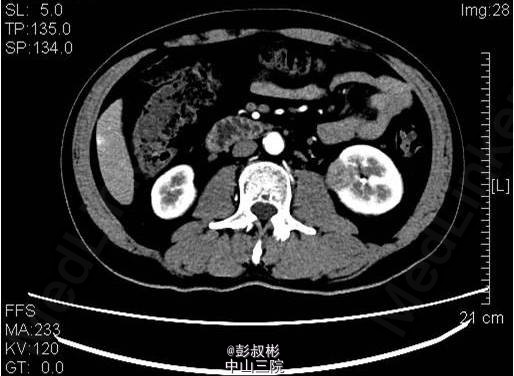

3、既往病史:高血压,高尿酸,高血脂6年,2013年行“右输尿管结石碎石取石术” 4、入院查体:未见明显异常体征。 5、影像学检查:中下腹部CT平扫+增强+CTU:左肾中盏可见结节状高密度影,直径约为6mm,基本同前。左肾下部可见大小约为36×21×23mm稍高密度影突出于包膜生长,较前明显增大,凸向肾外生长,浅分叶,其内见脂肪密度影,增强扫描可见轻度强化,病灶与左侧腰大肌关系密切。